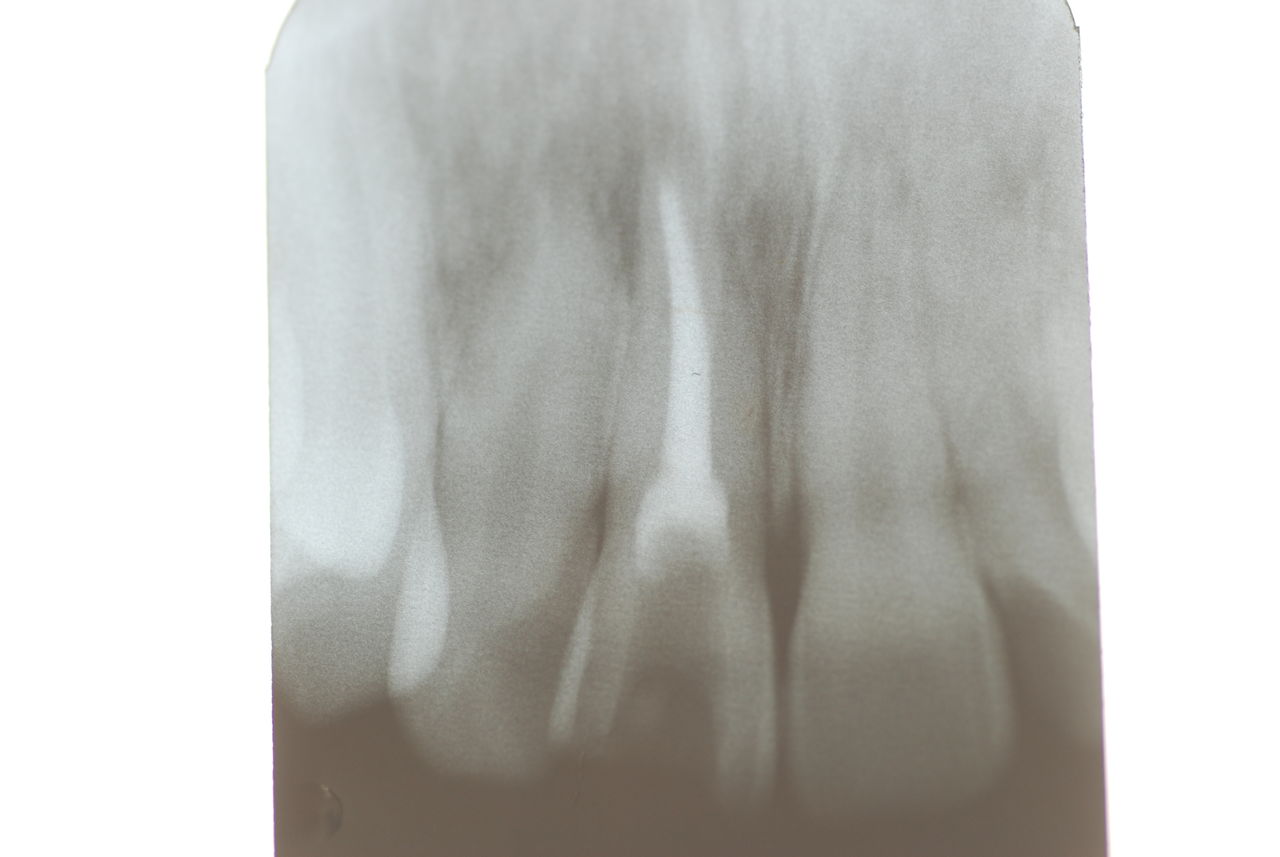

レントゲンと話の内容から、食いしばりや歯ぎしりによるものではなく、単純にぶつかる歯が少ないので、その時に前歯のところで何か硬い物などを噛んだために外傷性の痛みが来たのではないかという判断でした。炎症でもないので、奥歯にマウスピースなどを入れて前歯を当たらなくした後に、症状が緩解したら、反対咬合という上下の前歯の関係を簡単な小矯正で変更した方がいいという診断と治療方針の提案で解決しました。

2、67才、女性、主訴は噛みあわせがおかしい。

矯正している。左の上下の6才大臼歯を保険の金属冠から都内の某所でジルコニアという硬いセラミック?冠に変えてからおかしくなっていったそうです。担当の歯科医師は削ったりしてどちらの歯も当たっていないぐらい削っているに違和感が取れないという主訴です。兵庫県の先生からの相談でした。